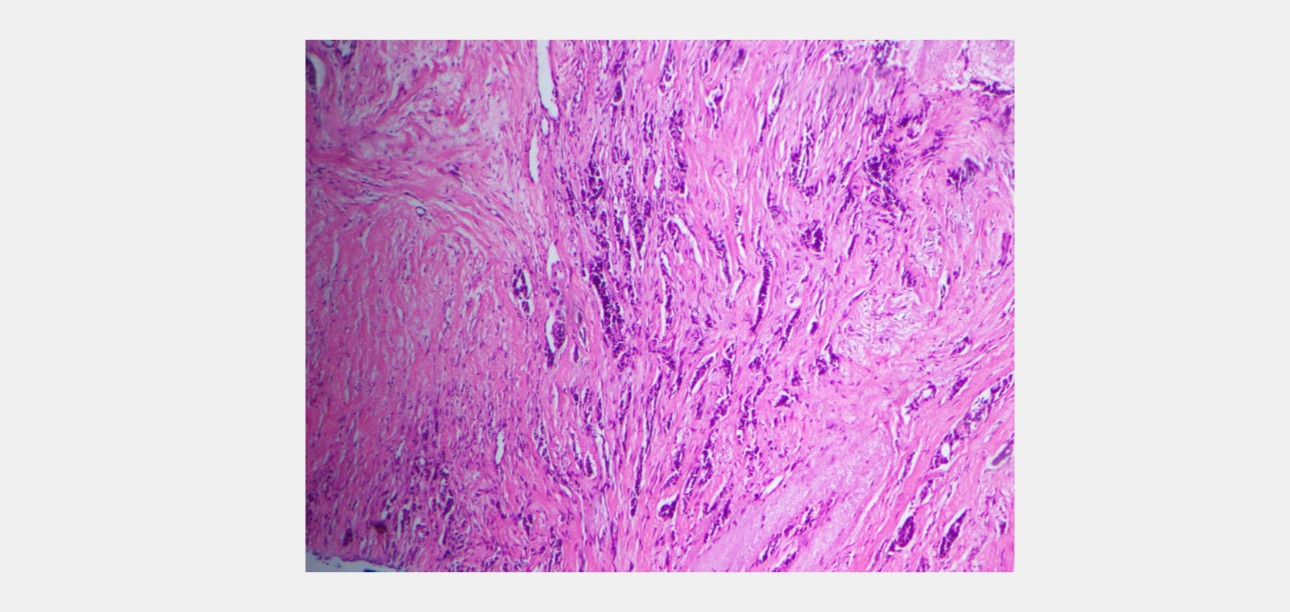

Histology Findings

6 core biopsy samples were taken. It showed an invasive carcinoma of the breast, composed of tubular structures, cords, and trabeculae of cells within a desmoplastic stroma. Tubule formation is minimal. The tumor cells have moderately pleomorphic vesicular nuclei. The mitotic count is 4/2 mm2. The cytoarchitectural features place the tumor in Nottingham grade II.

swe-prior-breast-mass-fig2-pc

Figure 2- Core biopsy specimen of the breast from patient A